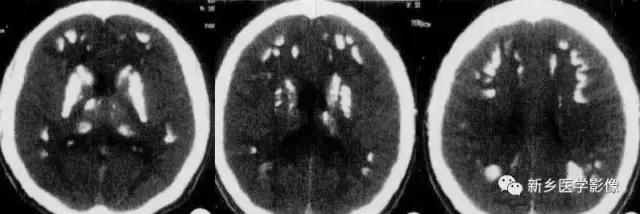

脑囊虫病慢性期,囊虫死亡以后,囊液逐渐被吸收,囊虫被机化,最后出现钙化。

钙化特点:多发、散在结节样钙化。钙化病灶通常较小、较圆、大小较均匀,少者单发或仅数个,多者可弥漫性分布于全部脑实质。